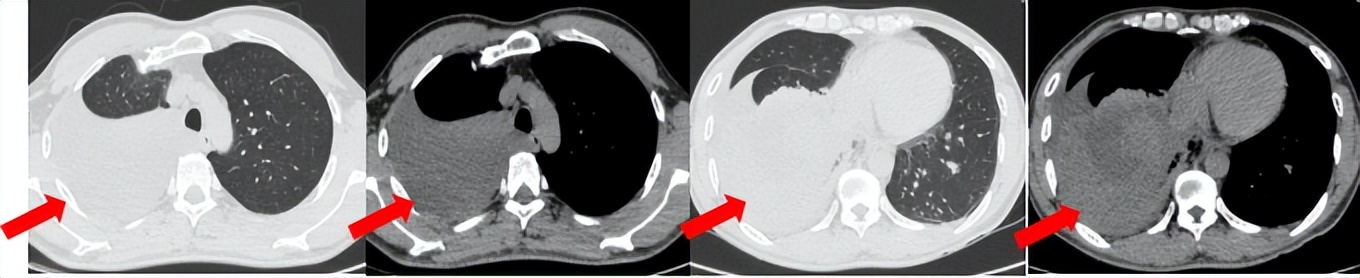

治疗经过:2024.08开始口服赛普替尼(160mg,bid)。2024.09复查胸CT评效PR。2025.1复查胸CT:右肺下叶外基底段见一不规则形实性肿块,大小约94mm×87mm,边缘呈分叶状,其内密度不匀。右侧胸腔见少许水样密度影。评效PD,PFS=5个月。患者未同意再次组织活检,目前应用卡博替尼治疗,仍在随访中。治疗期间未出现毒性反应。

2024.08

2024.09评效PR

2025.01评效PD